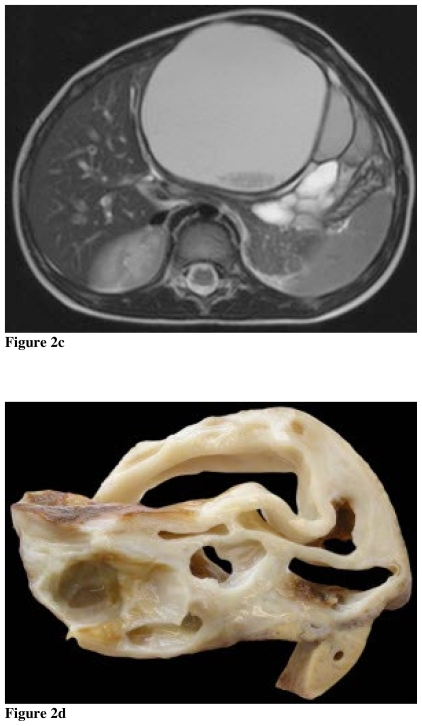

The MRI findings of mesenchymal hamartomas were reported for the first time in 1994 (6). In the interim, a series of twelve cases from the gastroenterology literature again demonstrated a spectrum of findings ranging from cystic to solid lesions. This series also depicted the relationship of lesion to the intrahepatic vessels (7). The MRI features reflect the underlying morphology of the lesion with cystic predominant lesions displaying high signal intensity on T2 weighted images, and variable intensity on T1 weighted images due to cyst contents. The intervening septations are of low signal intensity and display enhancement. These MRI findings are reflected in the case presented as well as an additional companion case of pathologically confirmed mesenchymal cystic hamartoma (Fig. 2). MRI is advantageous over other currently available imaging modalities because MRI has superb soft tissue characterization ability. Also, MRI with MRCP provides improved depiction of the biliary system which assists in surgical resection.

Figure 2.

Mesenchymal cystic hamartoma in a 4-year-old female. (a) Clinical image demonstrating distended abdomen at presentation (b), transverse US image of the liver showing a cystic mass in the left liver containing internal debris (c) axial T2W MRI image reveals the complex nature of the cystic high signal lesion with internal low signal debris (d) correlative gross pathologic specimen with “swiss cheese” like cystic channels.